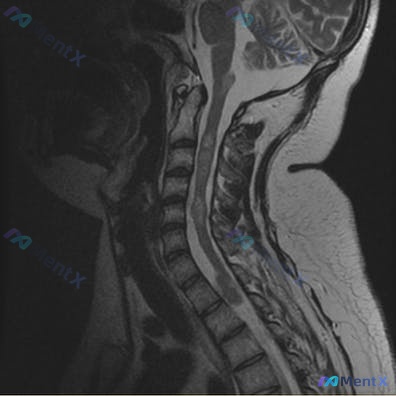

整理了一个很有意思的病例,第一眼很容易被常见病带偏。 基本情况:32岁女性 病史:6年前确诊双侧前庭神经鞘瘤,持续性面部感觉异常、听力损伤;无常规用药。 本次表现:上肢疼痛、无力,痛温觉减退(导致被热水烫伤)。 查体:双上肢肌力3/5,双上肢远端痛温觉分离。 影像:颈椎MRI提示生理曲度变直,C4/...